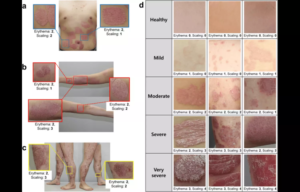

DMF Effectively Manages Moderate-to-Severe Psoriasis in Real-World Study

According to a new study, treatment with dimethyl fumarate provided…